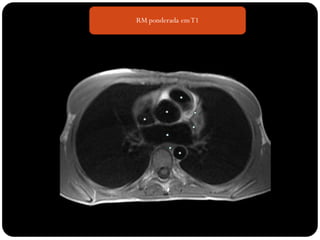

RM ponderada emT1